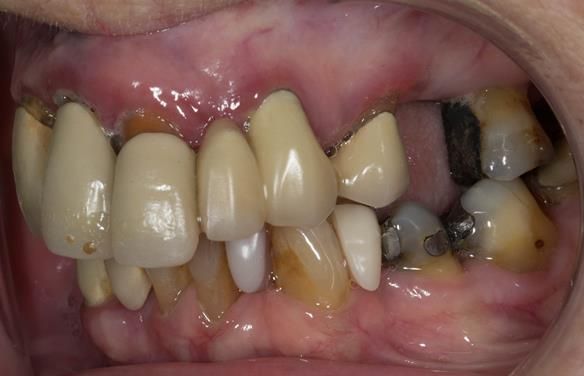

This 73 year old woman was referred to me by her general dental practiioner for treatment.

- “Upper teeth/crowns/bridges all loose”

- “Dentures seem the only option”

- “Bottom teeth are not good but still functional”

- The remaining natural upper natural teeth and lower back molars were heavily restored having generalised periodontitis stage 4 Grade C. Some of the teeth exhibited caries. The prognosis for these teeth ranged from dubious to hopeless.

- The lower teeth (apart from the lower back molars) had better progniosis and were to be managed by the referring general dental practitioner.

- The upper and lower acrylic based partial dentures exhibited suboptimal extension of the flanges and saddles. They had poor retention, support, stability and tissue fit.

- The patient had a high smile line showing 5mm or more alveolar soft tissue above the upper front teeth during social interaction.